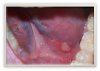

Oral lesions resulting from Crohn's include aphthous-type ulcerations (Figure 8), cobblestone mucosa, lip/facial swelling, orofacial granulomatosis, mucosal tags, xerostomia, angular cheilitis, and glossitis.18,19Treatment of the lesions can range from prescription drugs to homeopathic types of treatments, such as edible oils, acupuncture, and herbal remedies like ginseng. Dental professionals should work in tandem with the patient's primary care physician in order to identify the most effective treatment plan for that individual.

Fig 8. Aphthous-type ulceration.

Figure 8